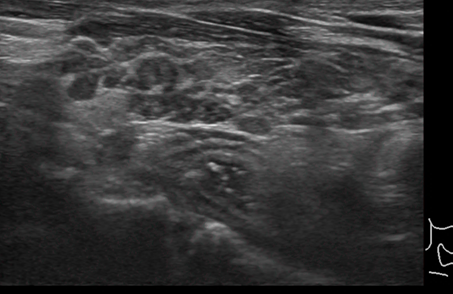

3) 갑상선 초음파

갑상선 조직의 변화나 염증 여부를 확인합니다. 갑상선 기능 저하증이 있는 경우 초음파로 보이는 갑상선의 모습이 다른 사람들보다 거칠어 보일 수 있습니다. 이러한 상태는 갑상선 결절을 구분하기 어렵기 때문에 일반인들보다 더 자주 초음파를 해보는 것이 좋습니다.